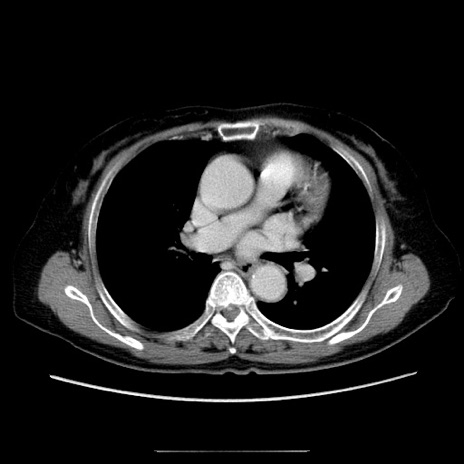

症例5(横断像)

【症例】70歳代女性

【主訴】お腹が張る

【現病歴】1週間くらい前から腹部膨満の自覚あり。昨日夜から増悪したため、本日救急外来受診。

【身体所見】意識清明、BT 36.5℃、BP 165/106mmHg、HR 80bpm、SpO2 98%、腹部:膨満、軟、自発痛・圧痛なし、触診にて不快感あり、腸蠕動音:減弱

【データ】WBC 12600、CRP 1.04